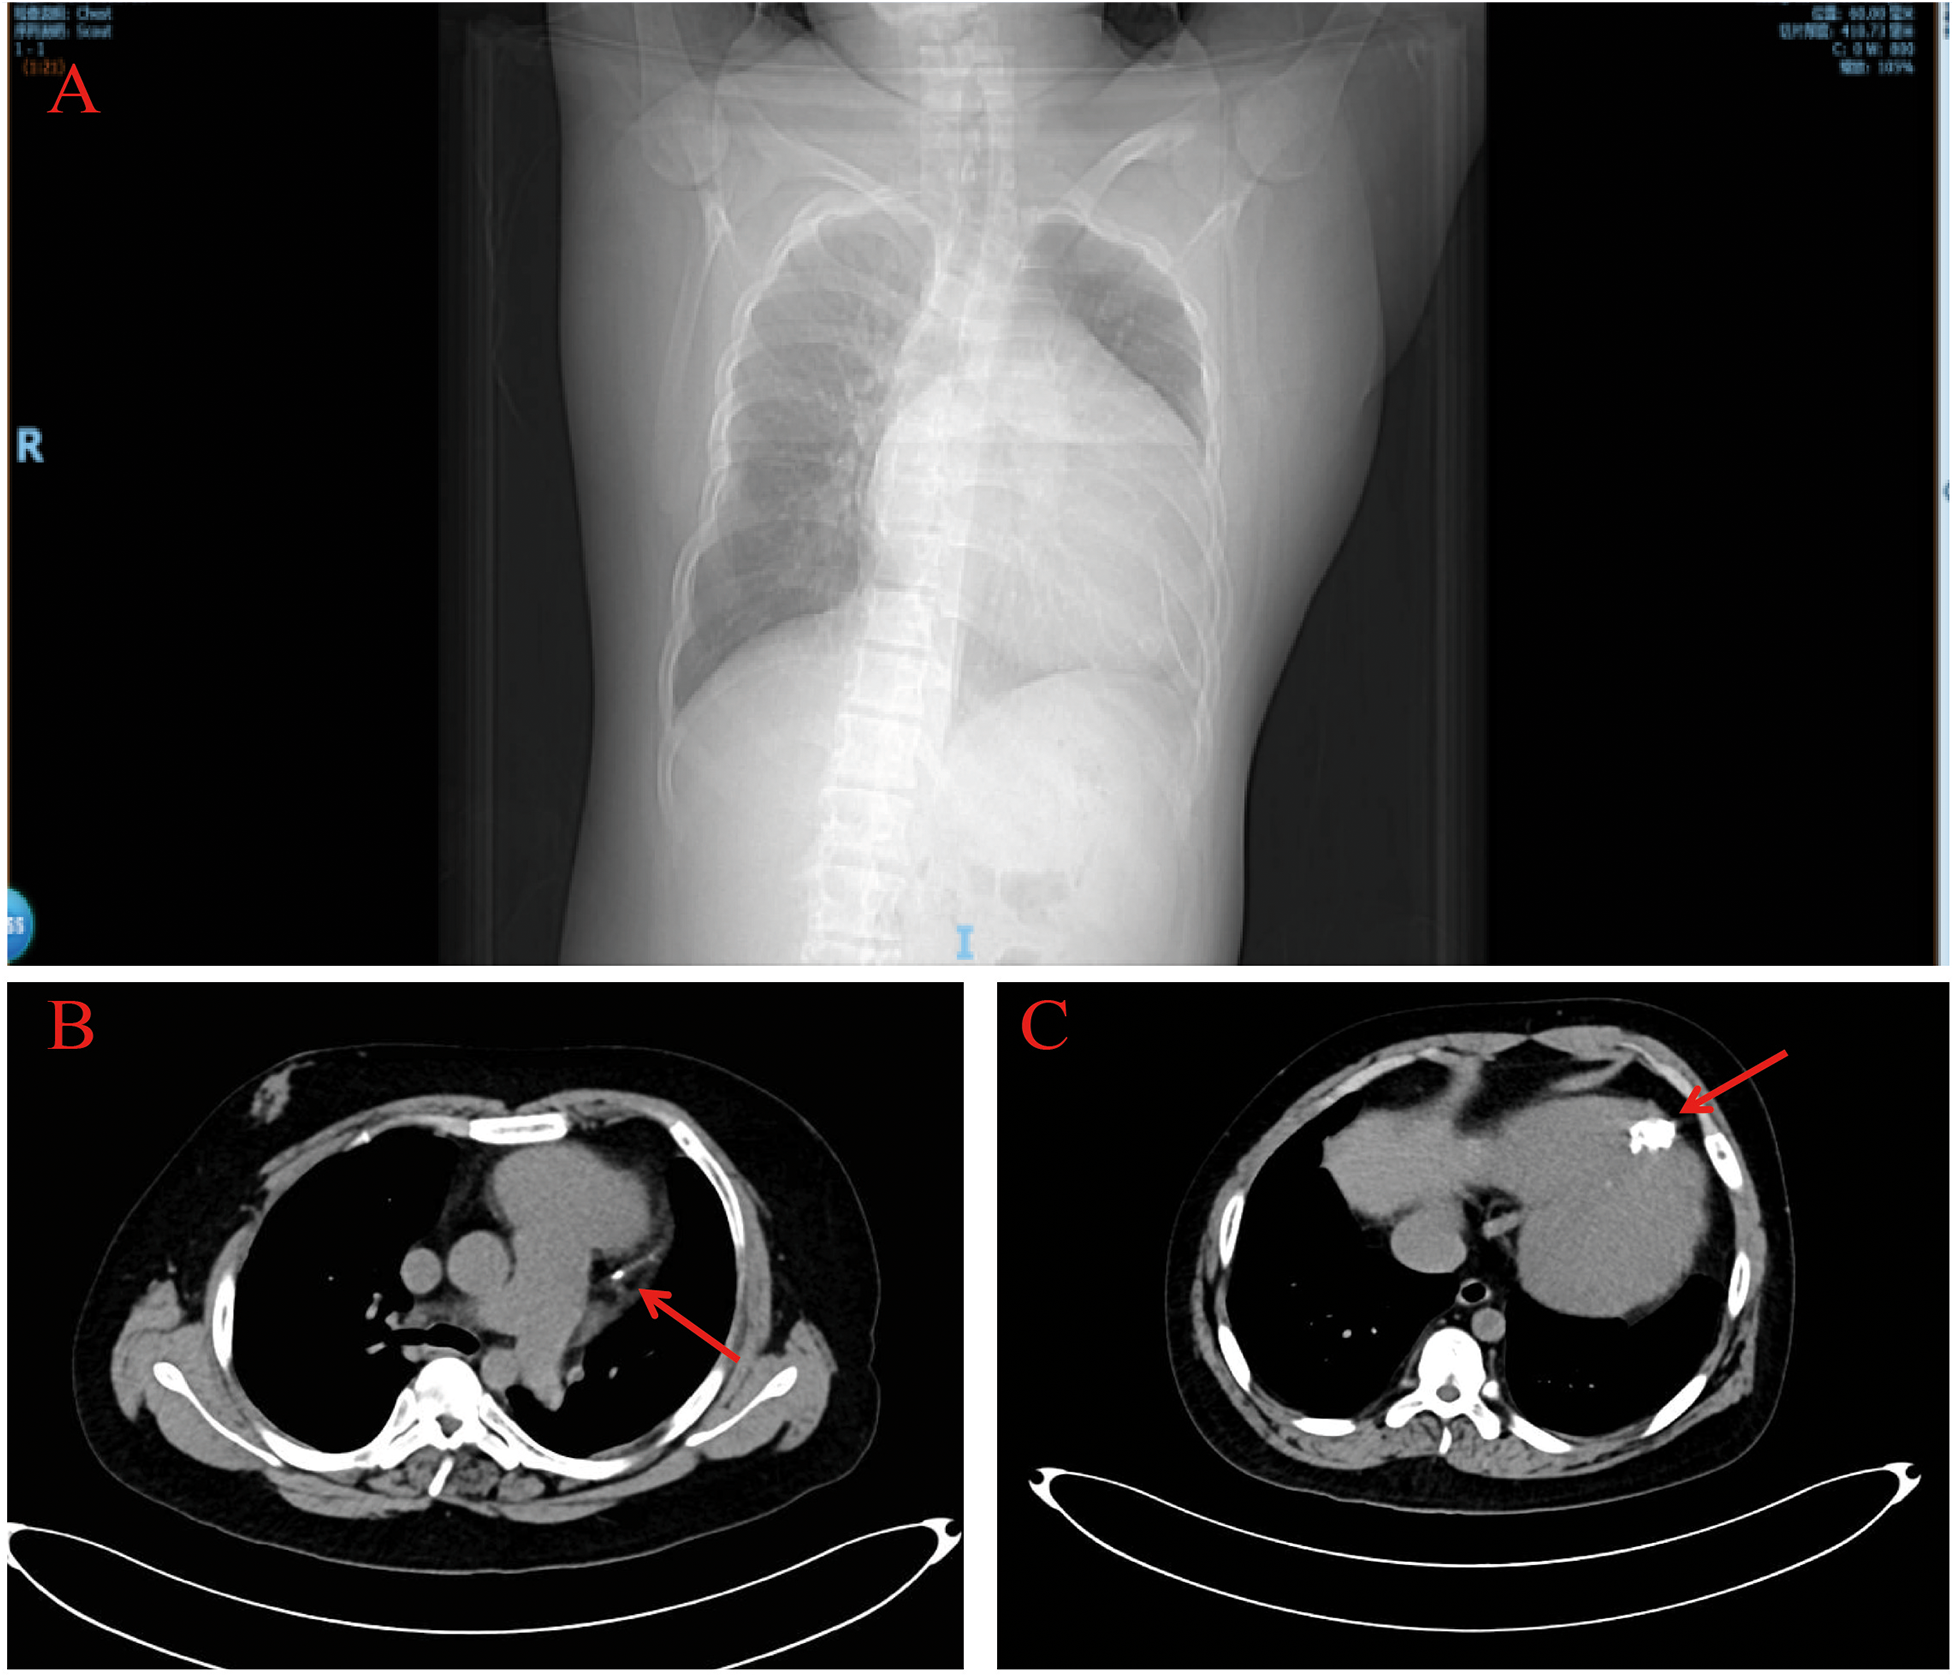

Chest contrast CT showed a markedly enlarged, globular heart (Figure 3A), linear calcification in the high lateral wall (Figure 3B, red arrow), and a hemispherical calcified lesion at the apex measuring about 3.0 × 4.0 cm (Figure 3C, red arrow).

Figure 3

Chest computed tomography. The chest computed tomography revealed a significantly enlarged, spherical heart (A) and calcifications at the cardiac apex (red arrows) (B,C).